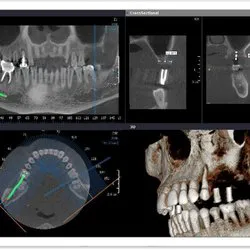

College Street Dental Photos